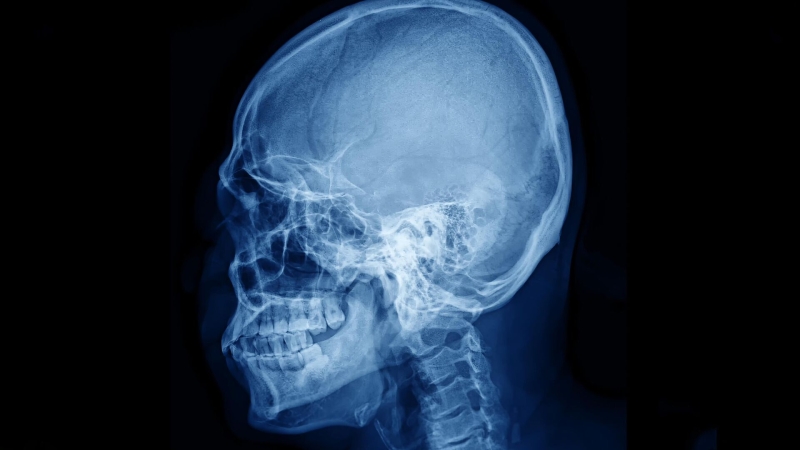

В настоящее время для того, чтобы увидеть сосуды мозга с хорошим качеством, часто приходится истончать кость или делать отверстие в черепе, поскольку костный материал сильно рассеивает лазерный свет и «смазывает» изображение. Именно лазерный свет используется в одном из распространенных методов наблюдения за кровотоком в головном мозге — лазерной спекл-контрастной визуализации, рассказал младший научный сотрудник лаборатории биомедицинской фотоакустики СГУ Юрий Сурков. Из-за рассеяния в кости получаются искаженные карты сосудов и перфузии головного мозга, добавил ученый.

Исследователи СГУ совместно с коллегами из Сеченовского университета, НМИЦ нейрохирургии имени Н. Н. Бурденко, НИУ МИЭТ и Университета Астон (Бирмингем, Великобритания) предложили способ примерно на 100 процентов увеличить контрастность карт сосудов, полученных при наблюдении мозгового кровотока через целый череп. Сосуды стали видны четче, а часть сосудистой сети, которая раньше терялась на фоне кости, проявилась и стала различимой.

«Представьте, что вы смотрите на пейзаж через матовое стекло: детали за ним расплываются, а картинка получается мутной. То же происходит, когда мы пытаемся увидеть кровоток в мозге сквозь череп любыми оптическими методами. Мы предлагаем два взаимодополняющих способа решения этой проблемы. Первый — сделать матовое стекло, а в нашем случае череп, временно более прозрачным. Второй — с помощью оптимизированных алгоритмов обработки данных отделить сигнал от движущейся крови от вкладов кости и других неподвижных структур, фактически «вычесть» влияние черепа из изображения», — объяснил Сурков.

Для увеличения прозрачности костей черепа ученые предложили использовать желтый пищевой краситель тартразин – разрешенную добавку Е102, которая используется в напитках, пюре, йогуртах и консервированных фруктах. «Цифровое» вычитание светового сигнала реализуется статистическими методами, различающими «полезный» и «мешающий» сигналы.

Когда эти два подхода используются одновременно, качество визуализации увеличивается и сосуды становятся видны гораздо отчетливее. Чем лучше виден мозговой кровоток, тем точнее можно оценивать, помогает ли лечение послеинсультных состояний или неврологических симптомов, как быстро восстанавливаются сосуды и какие зоны страдают сильнее, добавил Сурков.